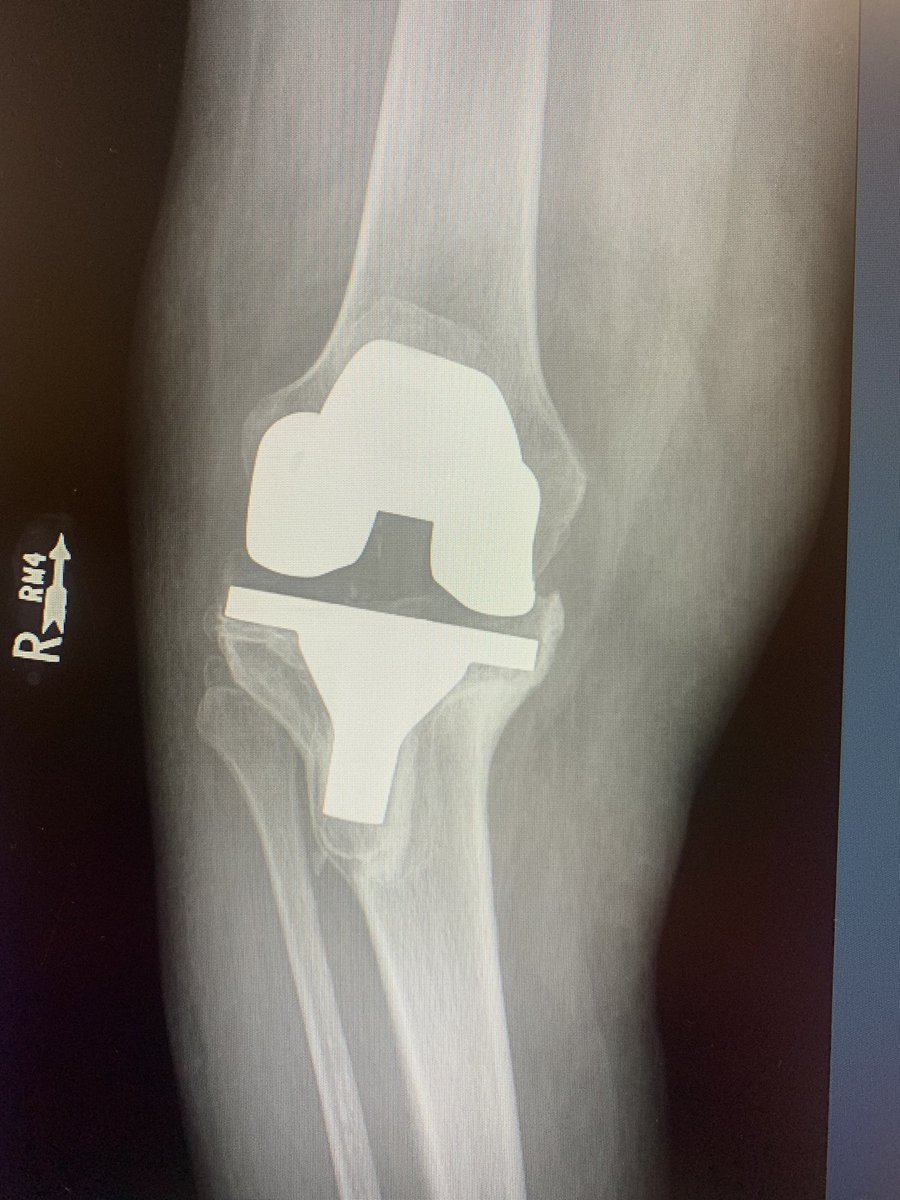

Borrowed this image from @instagram and shared on @LinkedIn Debate has ensued of whether this is real or #AI generated What says #orthotwitter

@generalorthomd @InvictaOrtho